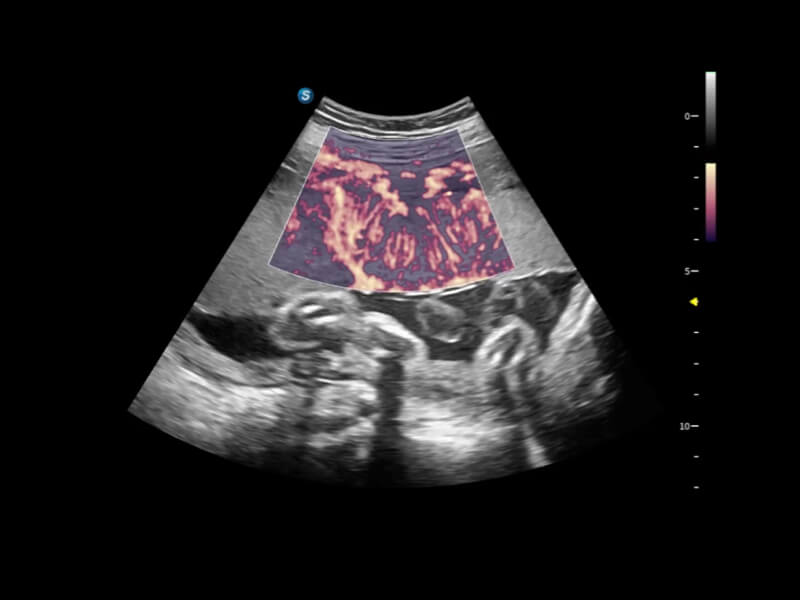

丰富的血流动力学检测技术,可在不同医疗场景中高效捕捉血流信号,助力临床诊疗。

在传统血流的基础上优化扫查和算法策略,能够更好的抑制组织信息,提炼红细胞运动信息,得到更高帧频,高灵敏度和分辨率的血流信号,还原更真实的血流动力学。

通过创新的Matrix E自适应滤波算法,能有效滤除软组织和噪声信号,最大限度保留超低速微细血流的信号;结合超长时间域算法,极大提升细微血流的敏感性和空间分辨率,更真实的反应组织、包块的血流灌注情况。